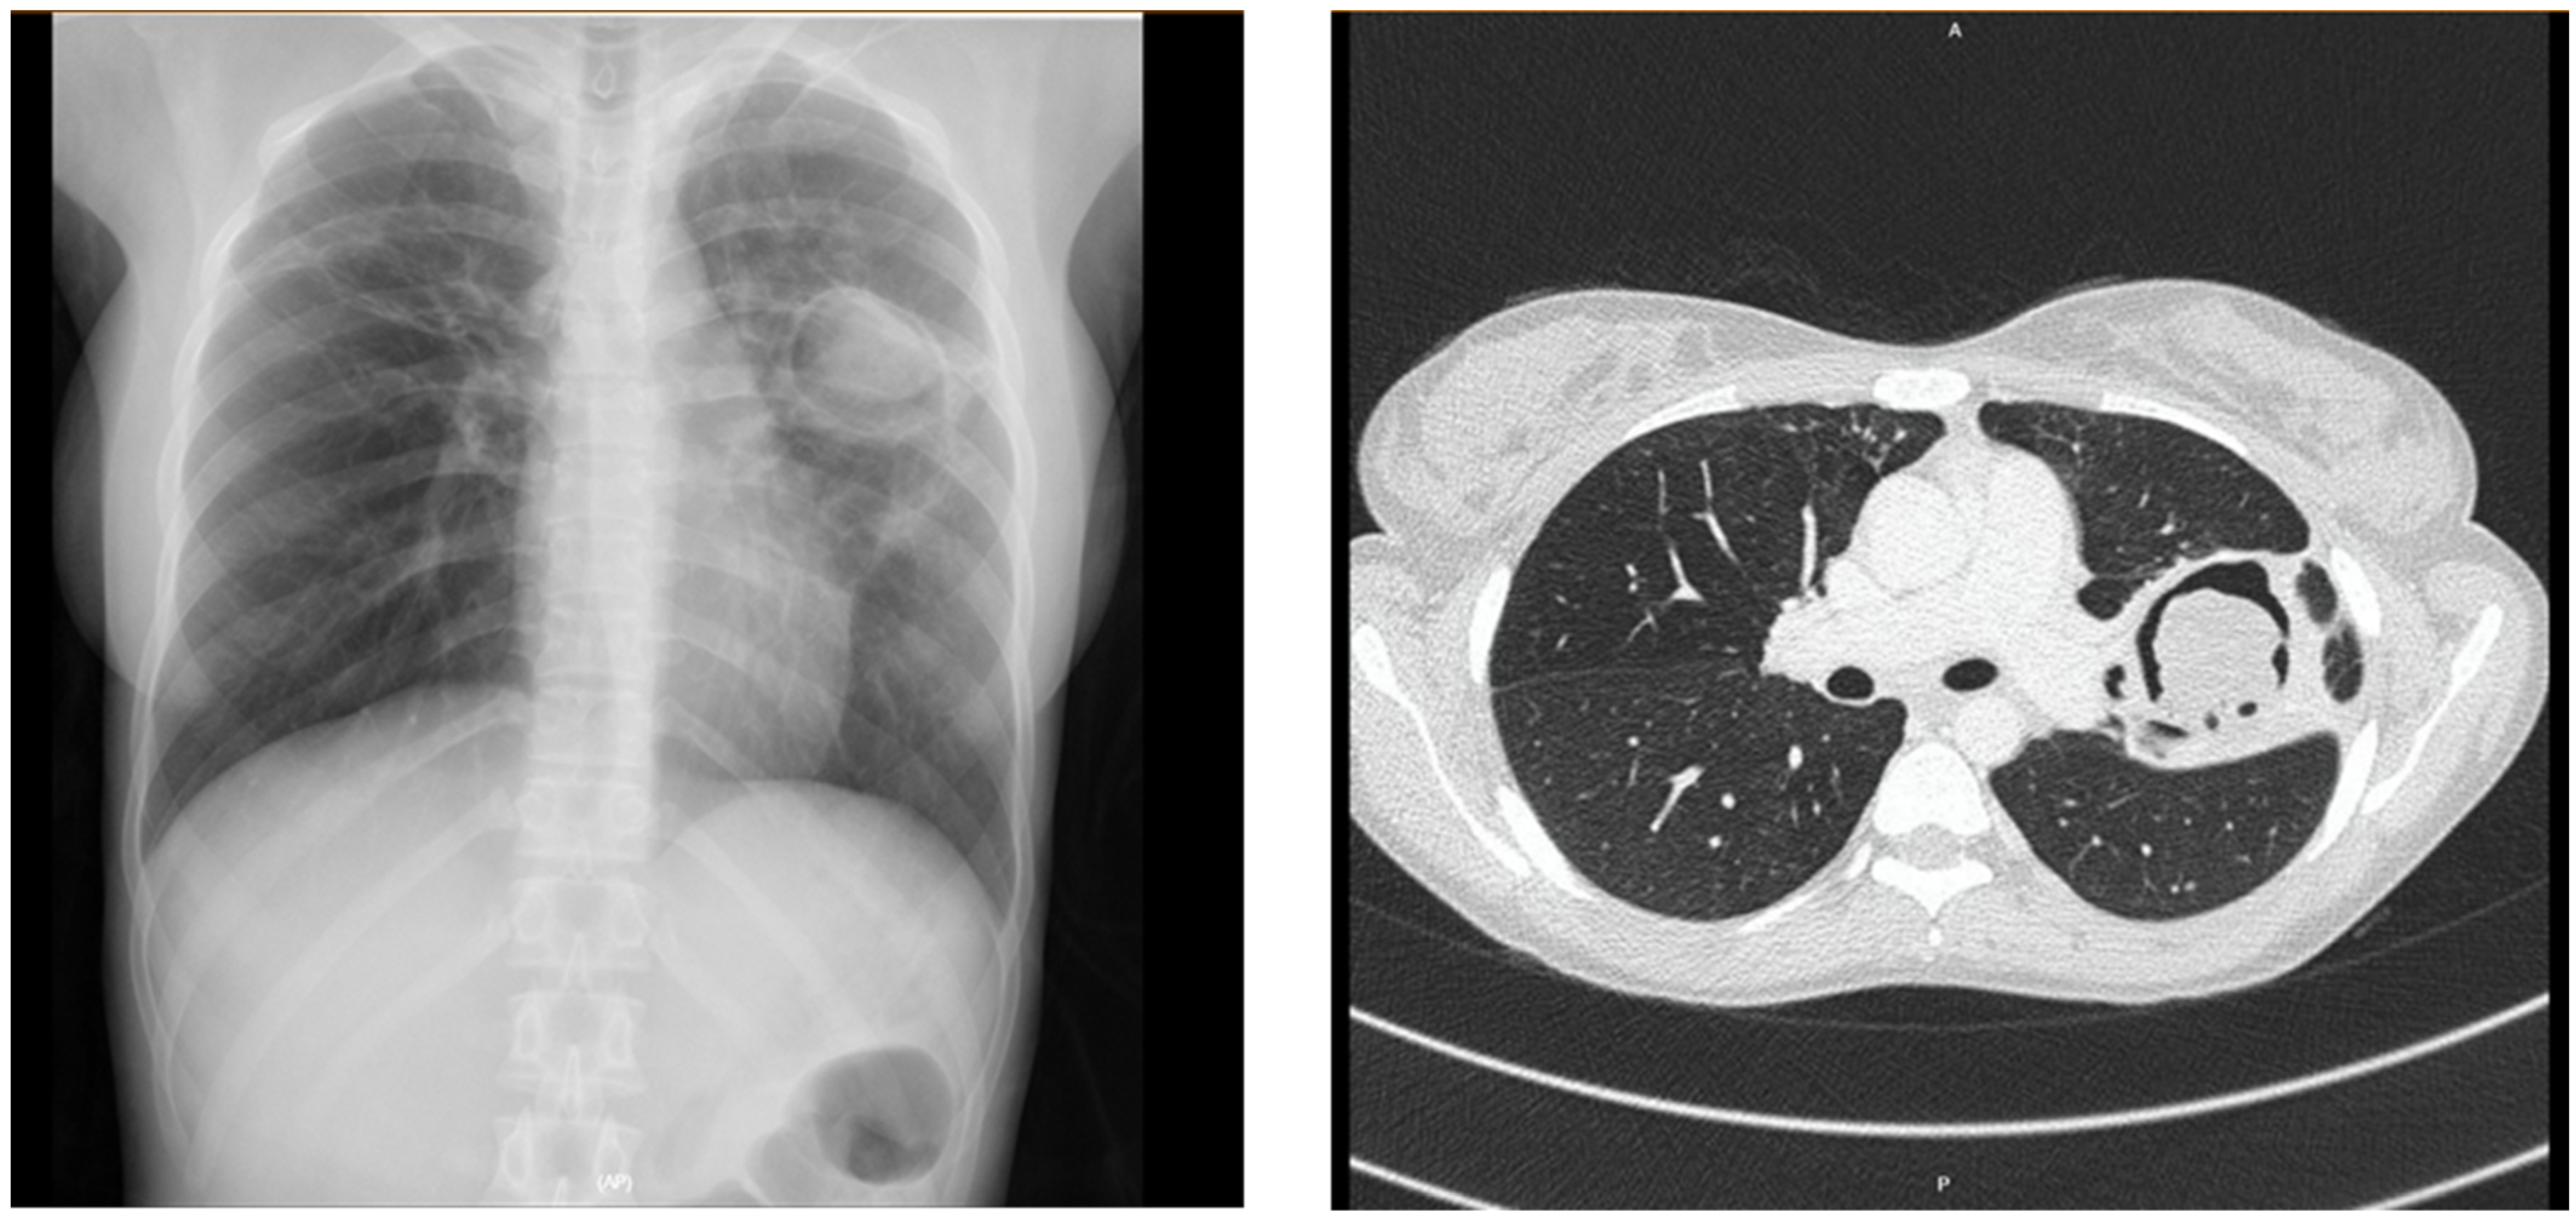

| Consolidation | 33 (33%) | 35 (47.3%) | 0.33 |

| Cavity | 22 (22%) | 61 (82.4%) | <0.001 |

| Pleural thickening | 10 (10%) | 24 (32.4%) | <0.001 |

| Bronchiectasis | 36 (36%) | 46 (62.2%) | 0.001 |